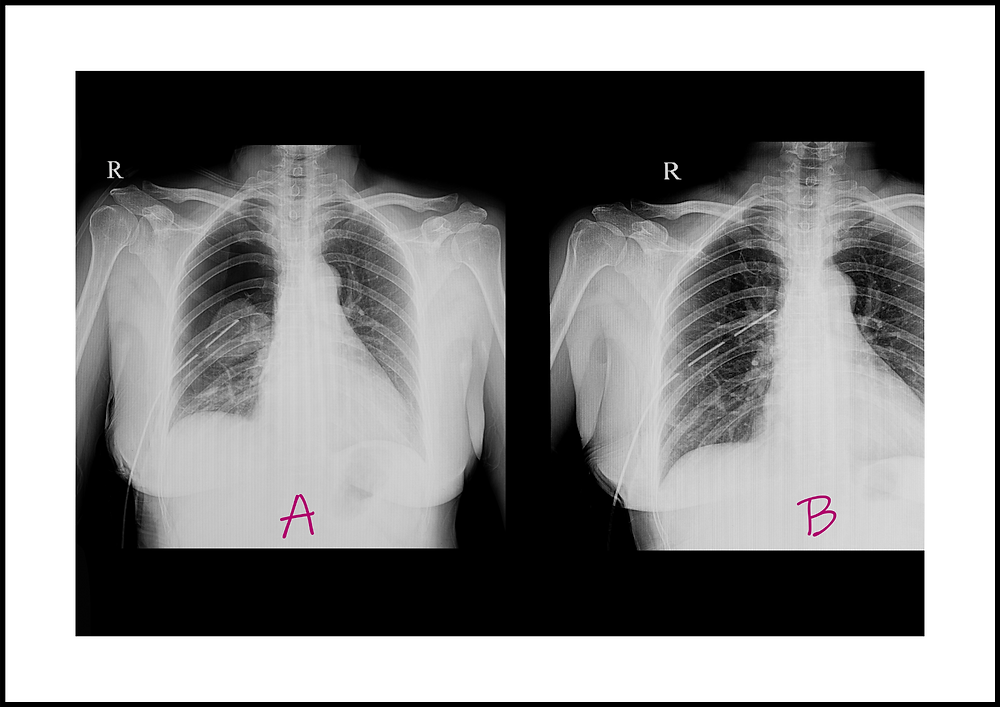

Appearance of pleural fluid and ascites. (A) Pleural fluid drained by

Appearance of pleural fluid and ascites. (A) Pleural fluid drained by Straw Color Pleural Fluid bloody fluid is most often caused by cancer, pulmonary embolus, or trauma; Under normal circumstances, a small amount of fluid is. (2) most effusions are non. interpreting pleural fluid results correctly requires an awareness of the possible aetiologies of a pleural effusion and an. pleural fluid analysis. (1) about one third are chylous. the color and. Straw Color Pleural Fluid.